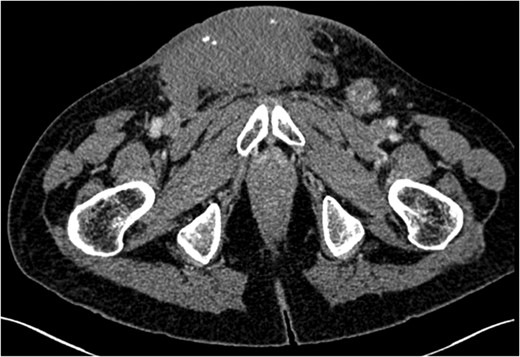

Seminomatous germ cell tumours characteristically affect men in their second-to-fourth decades, presenting as a testicular mass. Metastases when present are usually seen in para-aortic lymph nodes. These tumours are difficult to diagnose clinically and histologically when the presentation is unusual. We describe a seminoma presenting in a 61-year-old male as an inguinal mass with associated lymphadenopathy resembling lymphoma. Past medical history included ipsilateral cryptorchidism and orchidopexy. The tumour responded well to conventional chemotherapy.

Testicular tumours account for approximately 1% of all malignancies in men [1]. Up to 95% of testicular tumours are germ cell tumours (GCTs), which are subdivided into seminomatous and non-seminomatous tumours [2]. Histologically, seminomas may be further divided into three subtypes: classic, anaplastic and spermatocytic. Pure seminomas do not produce a specific tumour marker subset, but by definition have low levels of alpha-fetoprotein (AFP) and can have normal or mildly elevated beta-HCG (beta-subunit of human chorionic gonadotropin) [3]. Risk factors for the development of GCTs include cryptorchidism, Klinefelter's syndrome and testicular dysgenesis [4]. Testicular tumours commonly metastasize along gonadal vessels to the retroperitoneal lymph nodes [5]. Inguinal metastasis from a testicular seminoma is rare and likely related to previous inguinal or scrotal surgery causing disruption in normal lymphatic drainage [6]. We report a case of a massive seminoma presenting with primary inguinal lymph node metastasis in the absence of retroperitoneal lymphatic spread.

Testicular tumours account for approximately 1% of all malignancies in men, and they are the most common solid malignancy that affect males between 15 and 35 years old [2]. Up to 95% of testicular cancers are GCTs and the most common site for metastatic spread is the retroperitoneal lymph nodes. Inguinal lymph node metastasis is a rare occurrence and may be secondary to retrograde extension from significant retroperitoneal metastatic burden [5]. Primary involvement of inguinal nodes may be due to direct tumour invasion into the epididymis, breaching the scrotal wall or extension towards the vas deferens [7]. The large size of the tumour in our case suggests it is highly likely inguinal node involvement was via this route.

However, inguinal metastases have been reported in up to 10% of patients with a testicular tumour who have previously undergone orchidopexy or scrotal surgery [8]. It has been suggested that previous inguinal or scrotal surgery may lead to alteration in the usual patterns of lymphatic drainage. In our case, the history of orchidopexy for cryptorchidism could have been a significant factor for the absence of retroperitoneal lymphadenopathy despite the significant tumour burden at presentation. The overall risk of developing testicular cancer is greater in patients with previous cryptorchidism, occurring in 10% of GCTs [9]. Our case suggests that patients who have previously undergone inguinal or scrotal surgery may have alterations in normal lymphatic drainage leading to rare and atypical presentation of metastatic disease despite high tumour burden.